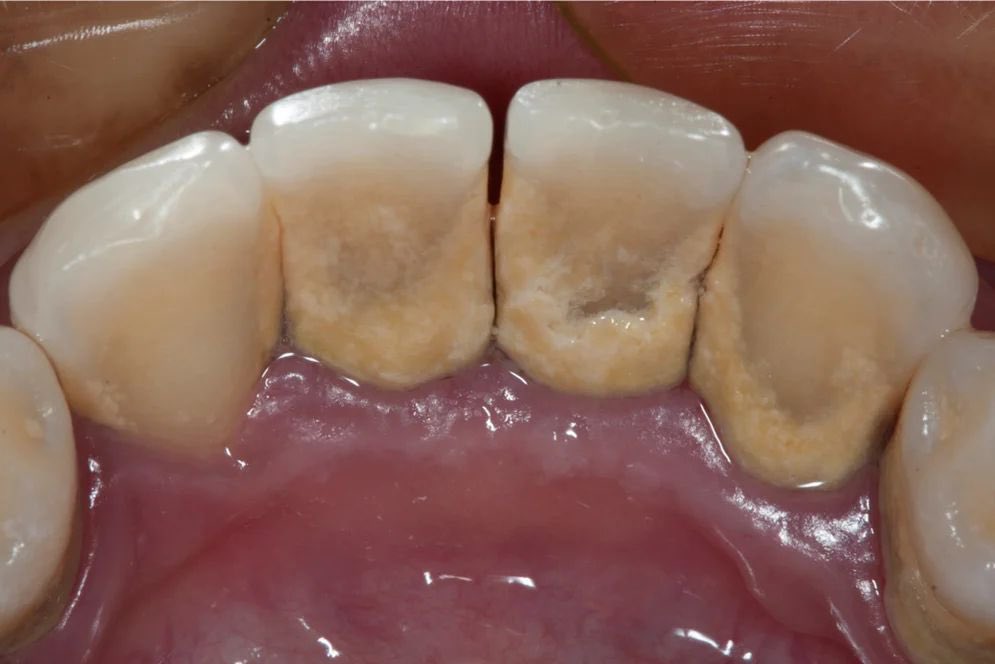

جير الأسنان هو طبقة صلبة خشنة تتكون على الأسنان نتيجة تراكم البلاك والمعادن، تترسب هذه الطبقة على الجزء الظاهر من السن أو أسفل خط اللثة، وتكون صفراء اللون أو بنية. وتعد أكثر المناطق شيوعًا لتراكم الجير في الأسنان هي السطح الخلفي للأسنان أو بينها.

ونظرًا لأن جير الأسنان شديد الصلابة فلا يمكن للشخص إزالته بتفريش الأسنان، بل لا بد من إزالته عند الطبيب بأدوات خاصة، وقد يؤدي تركه دون علاج إلى التأثير سلبًا على صحة اللثة والأسنان.

تشمل أعراض جير الأسنان ظهور ترسبات صلبة وخشنة على الأسنان خاصة بالقرب من اللثة أو بين الأسنان،

قد تظهر هذه الترسبات باللون الأصفر أو البني، حيث أن الجير به مسامات تجعله يتلون بفعل المأكولات والمشروبات التي يتناولها الشخص.